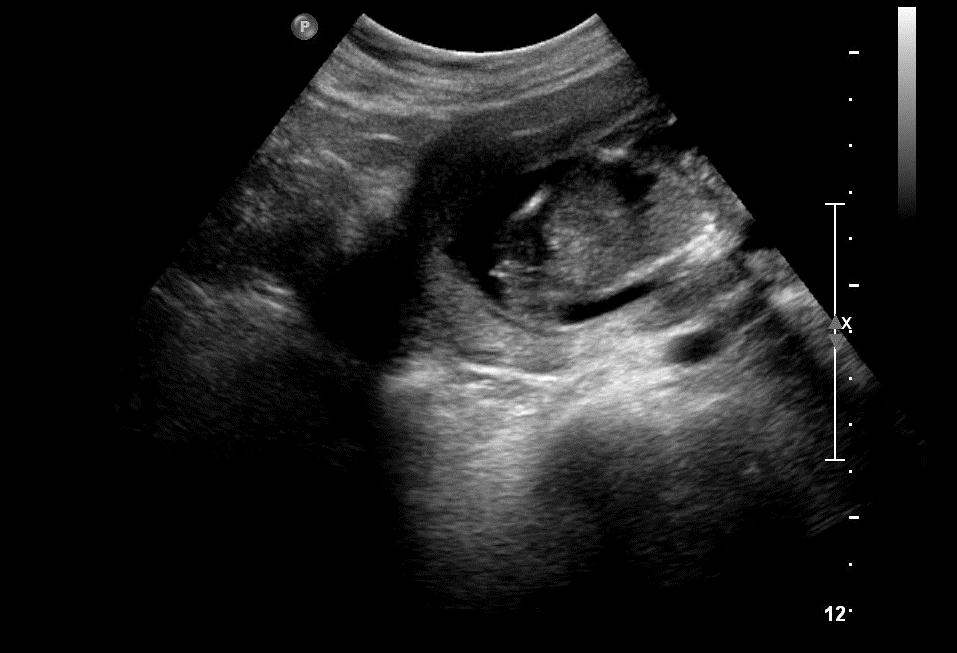

Attachment 3356Attachment 3357

Sono says, "GIRL?" But what's that in the middle?

I can't figure out what I am seeing.

I'm guessing the far left of the photo is where the sex is. It's not a potty shot but between the legs. However, we had a gender party yesterday. So, we never saw the sono explain their reasoning - just was told it was a girl.

I think we're seeing the baby's spine. The sono saw way more than we're seeing right here. What you could be seeing now could be a foot. I think you're good if they said girl :) Congratulations!!

Where is a potty shot? I would have guessed boy by the last shot.

True...didn't you get a potty shot, since this was for a private gender reveal?

Maybe boy?